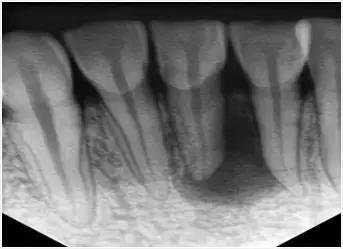

1、术前拍摄X光片

在根管治疗术前对牙齿拍X光片,以帮助诊断牙齿髓室的位置、根管数目及形态、测量根管工作长度以及为评价治疗效果提供对比的依据。